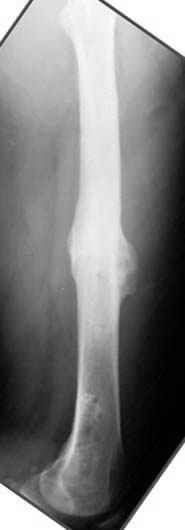

Отправитель: Djoldas Kuldjanov 23 Ноябрь 2004, 18:21

пластическая модель; и коррекция бедра аппаратом Илизарова.

Имею другие снимки тоже, получится как отчет о моей работе.

Отправитель: Evgueny Tschekashkin 24 Ноябрь 2004, 21:09

хотя даже если бы и инфекция , то nail exchange с рассверливанием канала - вариант дебрайдмента) Я думаю, что последовательность развития событий:

Узкий к-м канал - тонкий гвоздь- усталостный перелом дистальных винтов - развитие нестабильности и как ее результат остеолиз вокруг гвоздя - деформация анатомической оси бедра. Похоже, что я понял почему аппарат, а не новый гвоздь:-)

• Re: Hip joint

Отправитель: Alexander Chelnokov 24 Ноябрь 2004, 21:11

ET> хотя даже если бы и инфекция , то nail exchange с рассверливанием канала -

ET> вариант дебрайдмента)

Да, но если, скажем, течет из инфицированных каналов запирающих винтов, да инфекция в дистальном метафизе бедра - устанешь сверлить.

Аппарат в таком случае средство из серии "тише едешь - дальше будешь".

ET> Я думаю, что последовательность развития событий:

[...]

ET> деформация анатомической оси бедра.

Да, наверно. Но если ничего другого нету, ту небольшую деформацию можно было устранить дистрактором одномоментно ввести другой гвоздь.

Отправитель: Evgueny Tschekashkin 24 Ноябрь 2004, 21:13

> Да, но если, скажем, течет из инфицированных каналов запирающих винтов, да инфекция в дистальном метафизе бедра - устанешь сверлить.

ЕТ-Теоретически это возможно, а практически трудно представить - все-таки уровень медицинского сервиса высок, поэтому вряд ли инфекционное воспаление может зайти так далеко.....

ET> Похоже, что я понял почему аппарат, а не новый гвоздь:-)

> Тогда делись догадкой скорей!

ЕТ - Изначально костно-мозговой канал бедра был узкий, дальнейшее его рассверливание ещё больше скомпрометирует прочность бедра( латеральный кортекс дистального отломка уже истончен), приведет к дефекту наружной стенки - хотя это только мои догадки - хотелось бы знать мнение Джолдаса о выбранной тактике.